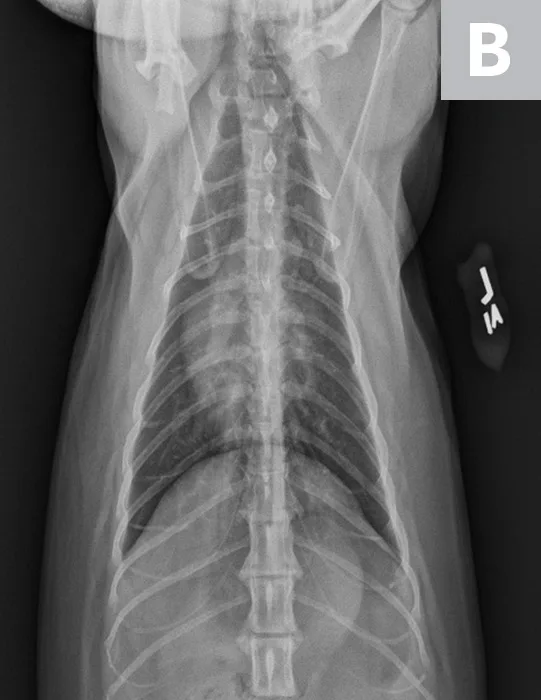

VHS calculation in a clinically normal cat using a left lateral radiograph (A). L (ie, long axis; 4.4) is drawn from the carina to the most ventral aspect of the apex. S (ie, short axis; 3.3) is drawn perpendicular to L at the widest aspect of the heart, extending to the cranial and caudal borders. S and L are transposed along the spine from the cranial aspect of T4 using calipers. The number of vertebrae traversed (rounded to the nearest tenth) are summed to calculate VHS (7.7). Orthogonal radiograph of the patient is also shown for more complete evaluation of cardiac silhouette (B).

Thoracic radiographs revealed a normal-sized cardiac silhouette with VHS 7.7 and no signs of CHF (Figure 1), as well as a redundant aorta caused by exaggerated horizontal positioning of the cardiac silhouette that increased the prominence of the aortic arch, a real and common age-related change considered normal in older cats.25 Remaining thoracic structures were unremarkable. Although heart disease could not be ruled out without echocardiography, there was no evidence of structural changes causing cardiac enlargement.